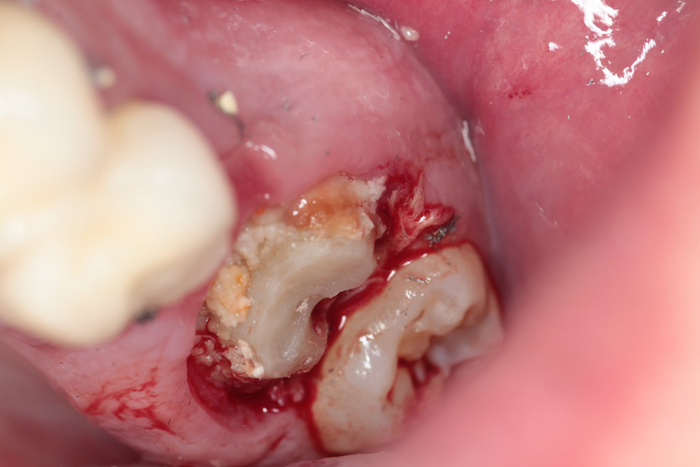

А если подобную коронку снять, то будет там вот такая кашка. Запах вы можете почувствовать через экран.